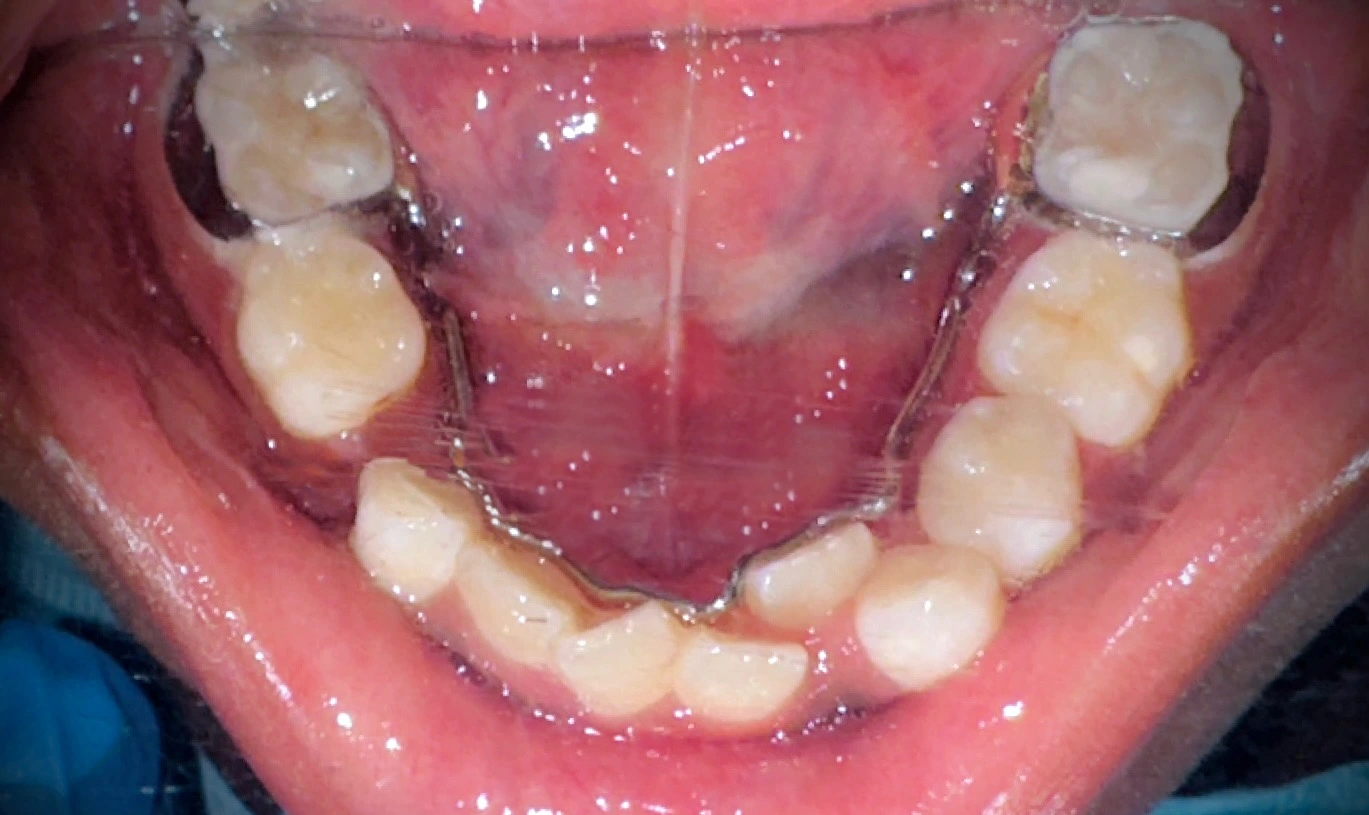

The complete clinical and radiographic evaluation, to include Orthopantomogram (OPG), exposed severe crowding of the lower anterior area, as well as premature loss of the lower left primary molar (#L), which leads to loss of space and causes the permanent teeth to migrate mesially. This diagnosis was sufficiently clear enough to result in the insertion of a fixed lingual holding arch with U loops to ensure space and support the symmetry of the arch until a natural eruption of successors.

The lingual holding arch was cemented with glass ionomer cement, which is adhesive and releases fluoride, as this gave an opportunity to expand the U-loops and adapt them to the lingual tooth surfaces. The process was done with a lot of care using a rubber dam to keep everything clean, and special tools were used to ensure the appliances were placed correctly.